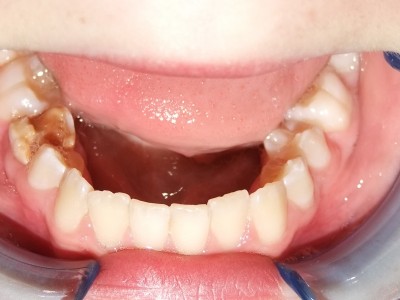

Voor behandeling